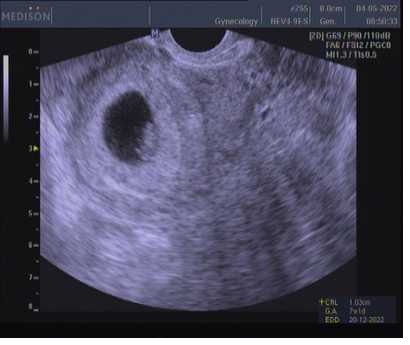

Prvni fotka 7+1 a druha 9+4 😊😊

@vero987nika prvni fotka začátek 10tt druhá fotka 4tt